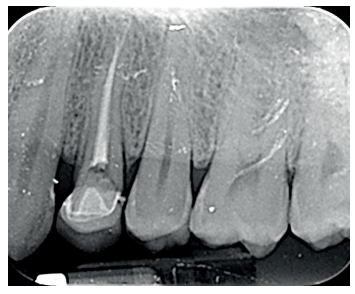

Se presenta en el Máster en Cirugía Oral, Implantología y Periodoncia de la Universidad Alfonso X El Sabio (Madrid, España) un paciente de 24 años derivado para exodoncia del primer premolar superior izquierdo y colocación inmediata de implante debido a una fractura corono-radicular como consecuencia de caries asintomática, con margen distal 2 mm subgingival y limitada estructura remanente (Figuras 1 y 2). Después de un estudio completo del caso, en colaboración con el Máster en Endodoncia de la misma facultad, se planificó la realización de la extrusión quirúrgica, endodoncia y posterior rehabilitación del diente. Dentro de este estudio resultaron de vital importancia las pruebas radiológicas, compuestas por radiografías periapicales y CBCT, que confirmaron la compatibilidad de la anatomía radicular con la realización de una extrusión mínimamente traumática.

con fractura corono-radicular.

fractura corono-radicular.